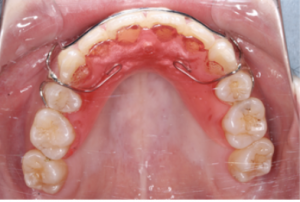

リテーナーの場合には透明なマウスピース型を使用する場合もあれば、ワイヤーとレジンで作られたプレート型を使用する場合もあります。

プレート型のリテーナー